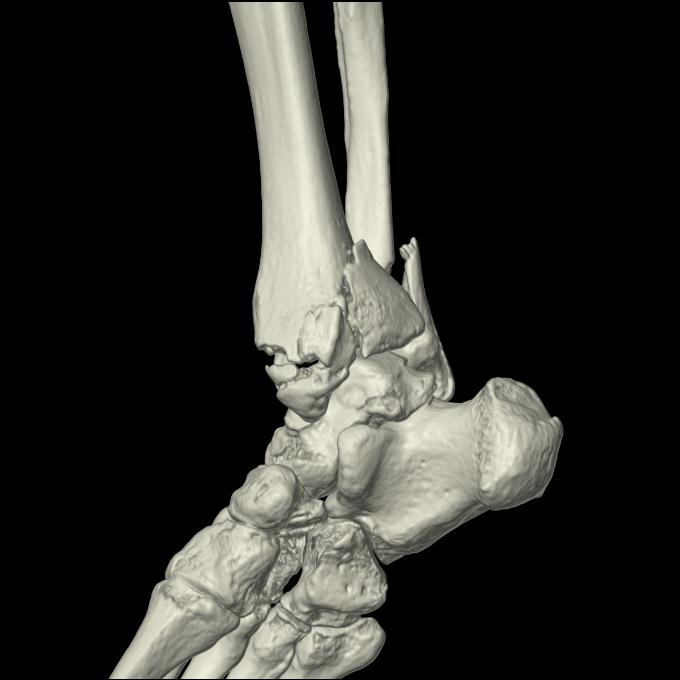

56476 8/28 4R 1/21 2R 左足関節 デジカメ写真 72歳女性 右足関節AS

102755 1/4 2R 1/15 2R 右足関節 68歳女性 右三果脱臼骨折